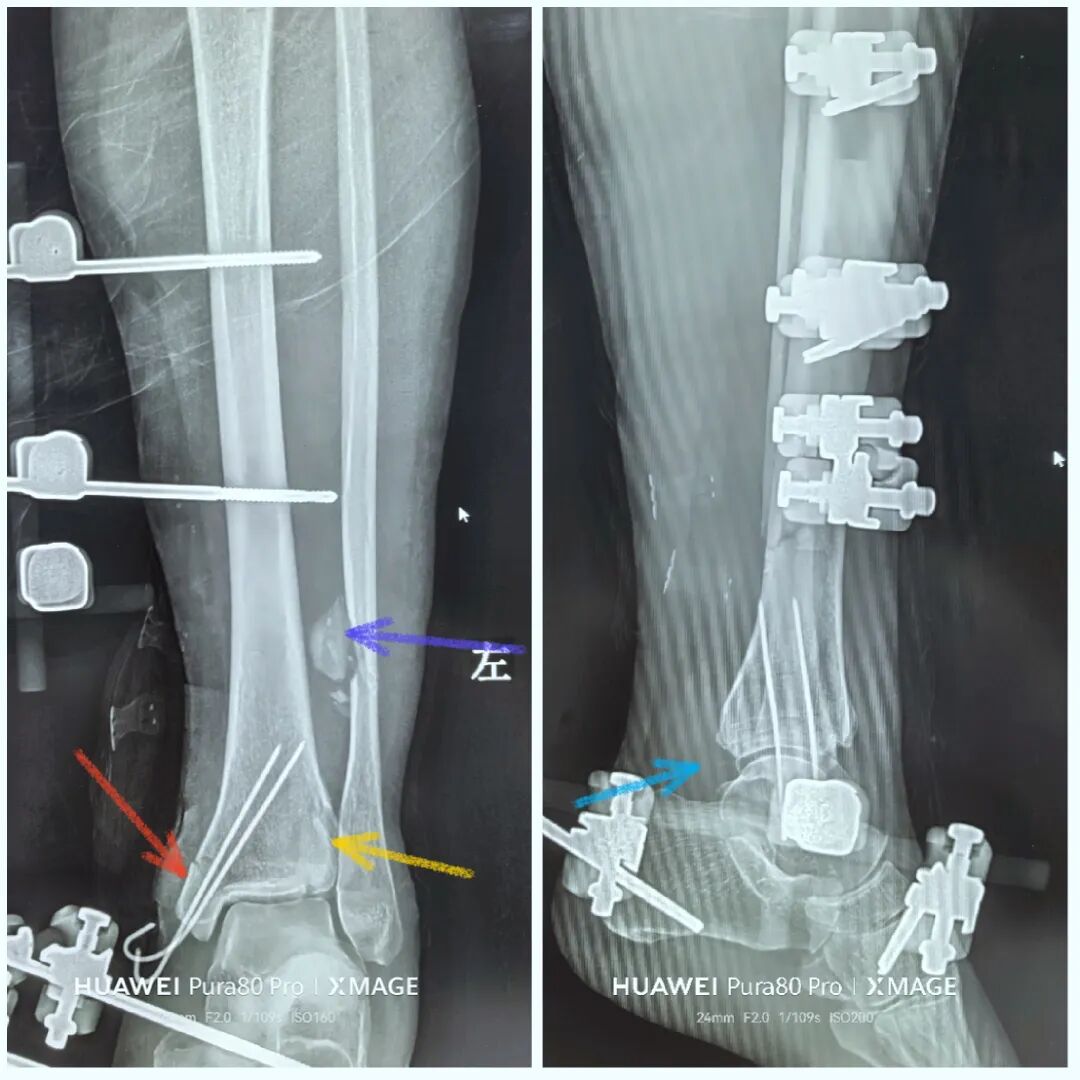

没有松外架

骨折没复位

松外架后,保持踝关节中立位

依靠软组织铰链复位后踝

拉力钉40,拉过了,复位过头了

图片

换钉子,调整下方向

解剖复位

最后做下胫腓

内踝间隙还是大

两个位置螺钉固定

下胫腓关节复位

内踝间隙恢复